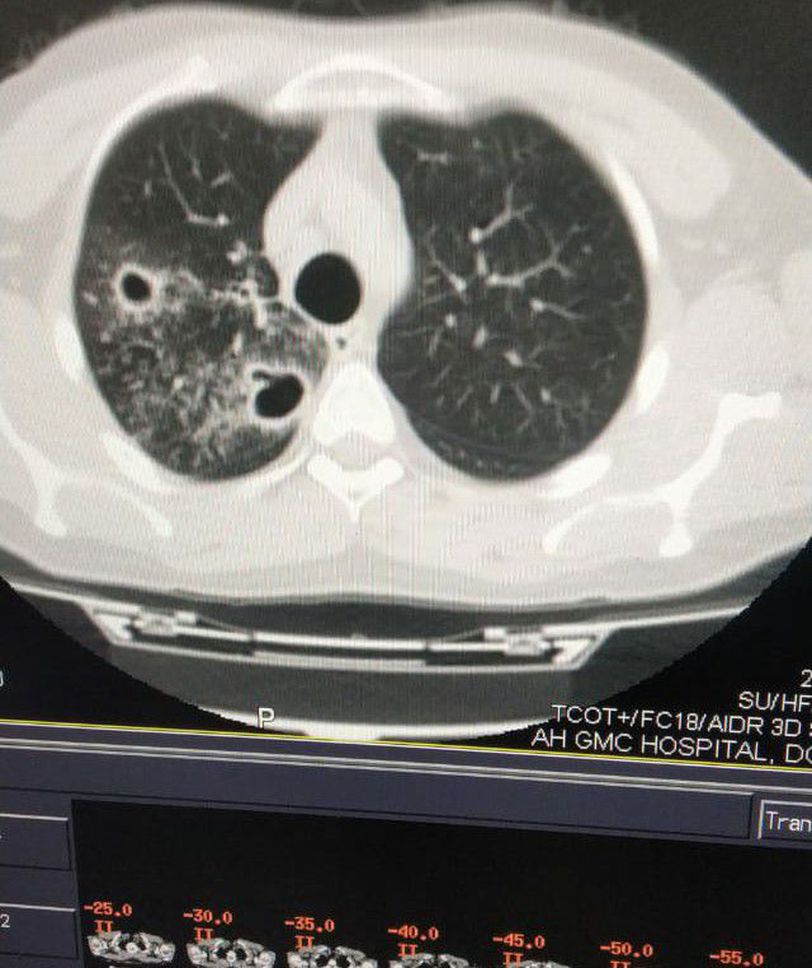

HRCT chest

I am confused with black 2 cavities in right lung And with white spots ..and patients covid report is negative

Cystic Bronchiectasis

Klebsiella,staph, aspergillosis

I'd say tuberculosis

Aspergillosis

Plain c.x.r taken already...it shows bilateral bronchitis, and spots

Staph aureus

Bronchiectasia

I think bronchiectasis with a chance of aspergillus infxn